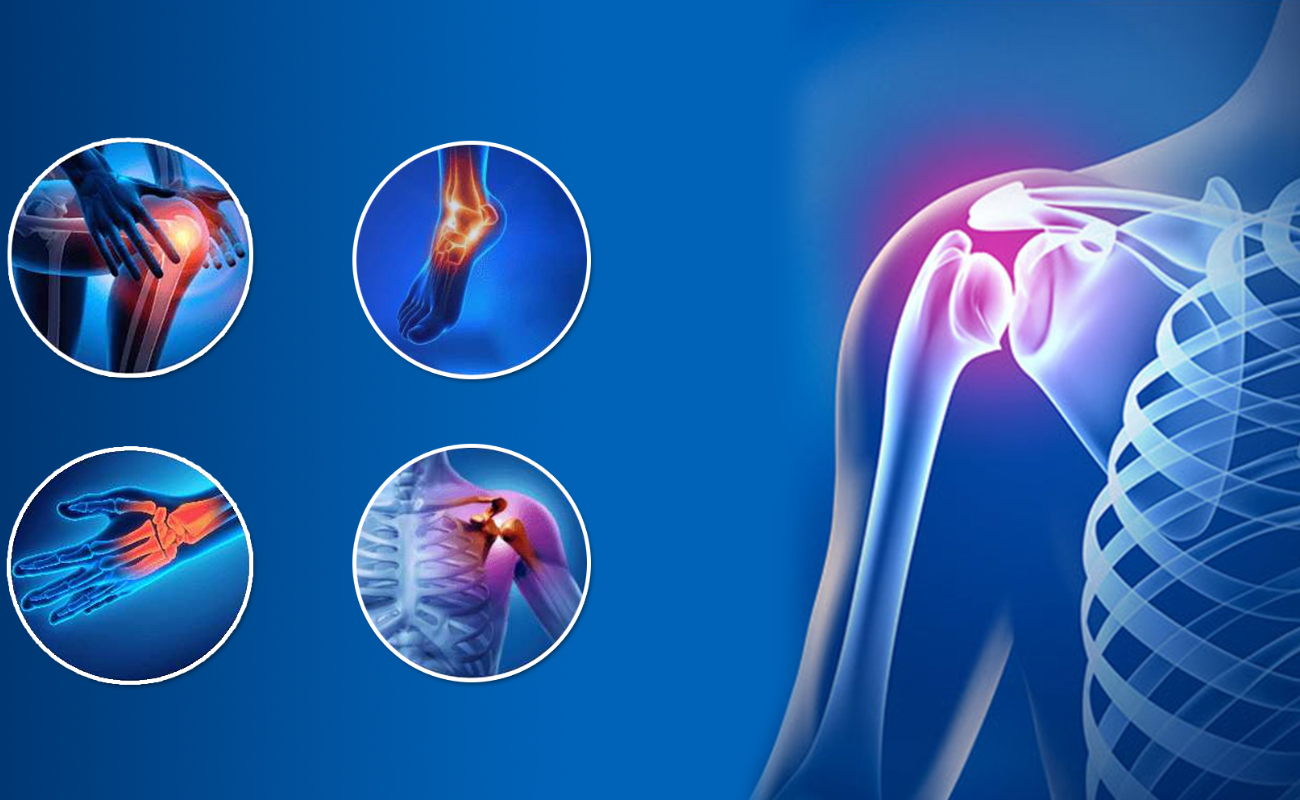

Understanding Common Orthopedic Conditions: Causes, Symptoms, and Treatments

Orthopedic conditions encompass a wide range of disorders that affect the musculoskeletal system, including bones, joints, muscles, ligaments, tendons, and nerves.

Advanced Treatment for Arthroscopy and Sports Medicine

For a sports person or an athlete, injuries mean a major disruption either in their career or routine. Be it a minor or major injury, it doesn’t take time for them to become an inconvenience.